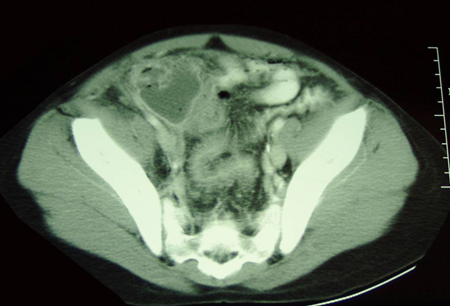

- CT scan abdomen and pelvis:

target lesion: intraluminal soft-tissue density mass with an eccentrically placed fatty area; reniform mass: high attenuation peripherally and lower attenuation centrally; sausage-shaped mass: alternating areas of low and high attenuation representing closely spaced bowel wall, mesenteric fat and/or intestinal fluid and gas

更多 - CT scan abdomen:

thickened inflamed bowel mucosa, thumbprinting, intestinal dilation or evidence of stricture; inflamed mesentery; intra-abdominal abscesses

更多 - CT scan abdomen and pelvis:

skip lesions, bowel wall thickening, surrounding inflammation, abscess, fistulas

More - CT scan abdomen:

dilated small intestine; may demonstrate a transition zone of obstruction, mass, tumour, abscess

- CT scan abdomen:

bowel obstruction with whirl pattern of mesentery

More - CT scan abdomen and pelvis:

gaseous distension of large bowel; may demonstrate a transition zone of obstruction